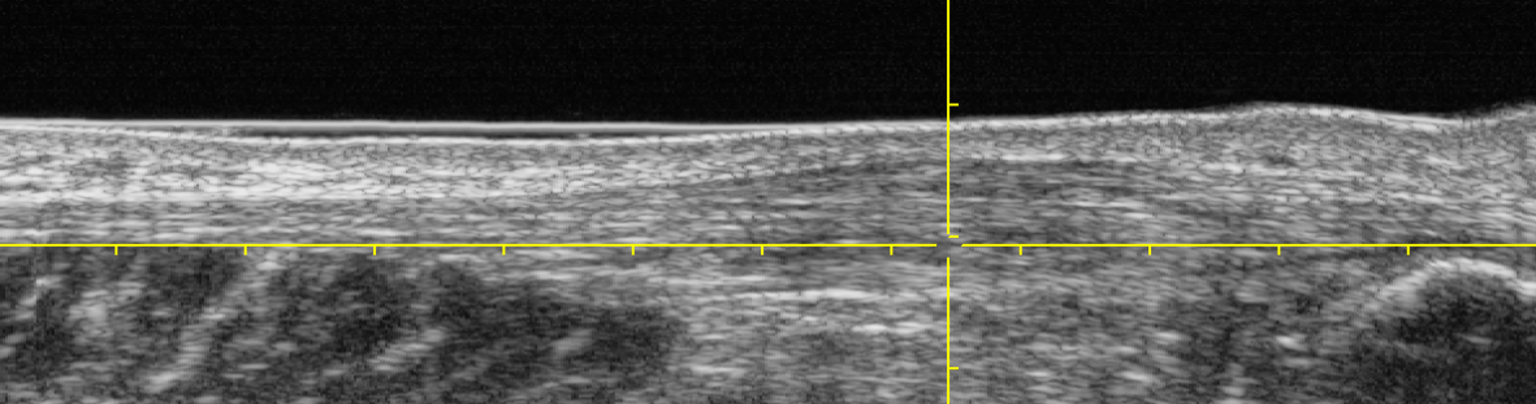

Role of Ultrasound Tissue Characterisation (UTC)

Ultrasound tissue characterisation plays a crucial role in diagnosing and understanding the nature of Achilles tendon pain. It provides a non-invasive, readily available, and cost-effective way to visualize the tendon’s structure and identify abnormalities that may be causing pain. Due to its detail it helps guide the best treatment for your tendon.

UTC Scan is able to provide:

– Grey scale 3D Scan of the tendon

– UTC Analysis of tendon fibre types

– Statistical analysis of tendon fibres

– Accurate identifiction of affected fibres and how to target       rehabilitation